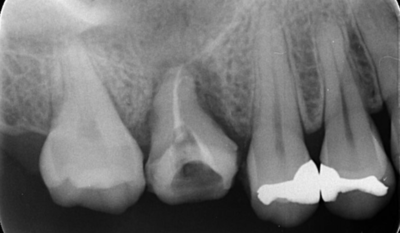

初診時デンタルX線写真

初診時デンタルX線写真とCT画像。

根管外に不透過像とそれを取り囲む透過像を認める。

コアを除去すると、分岐部へつながるパーフォレーションを認めた。

これが排膿の原因であったため、保存は困難と判断した。